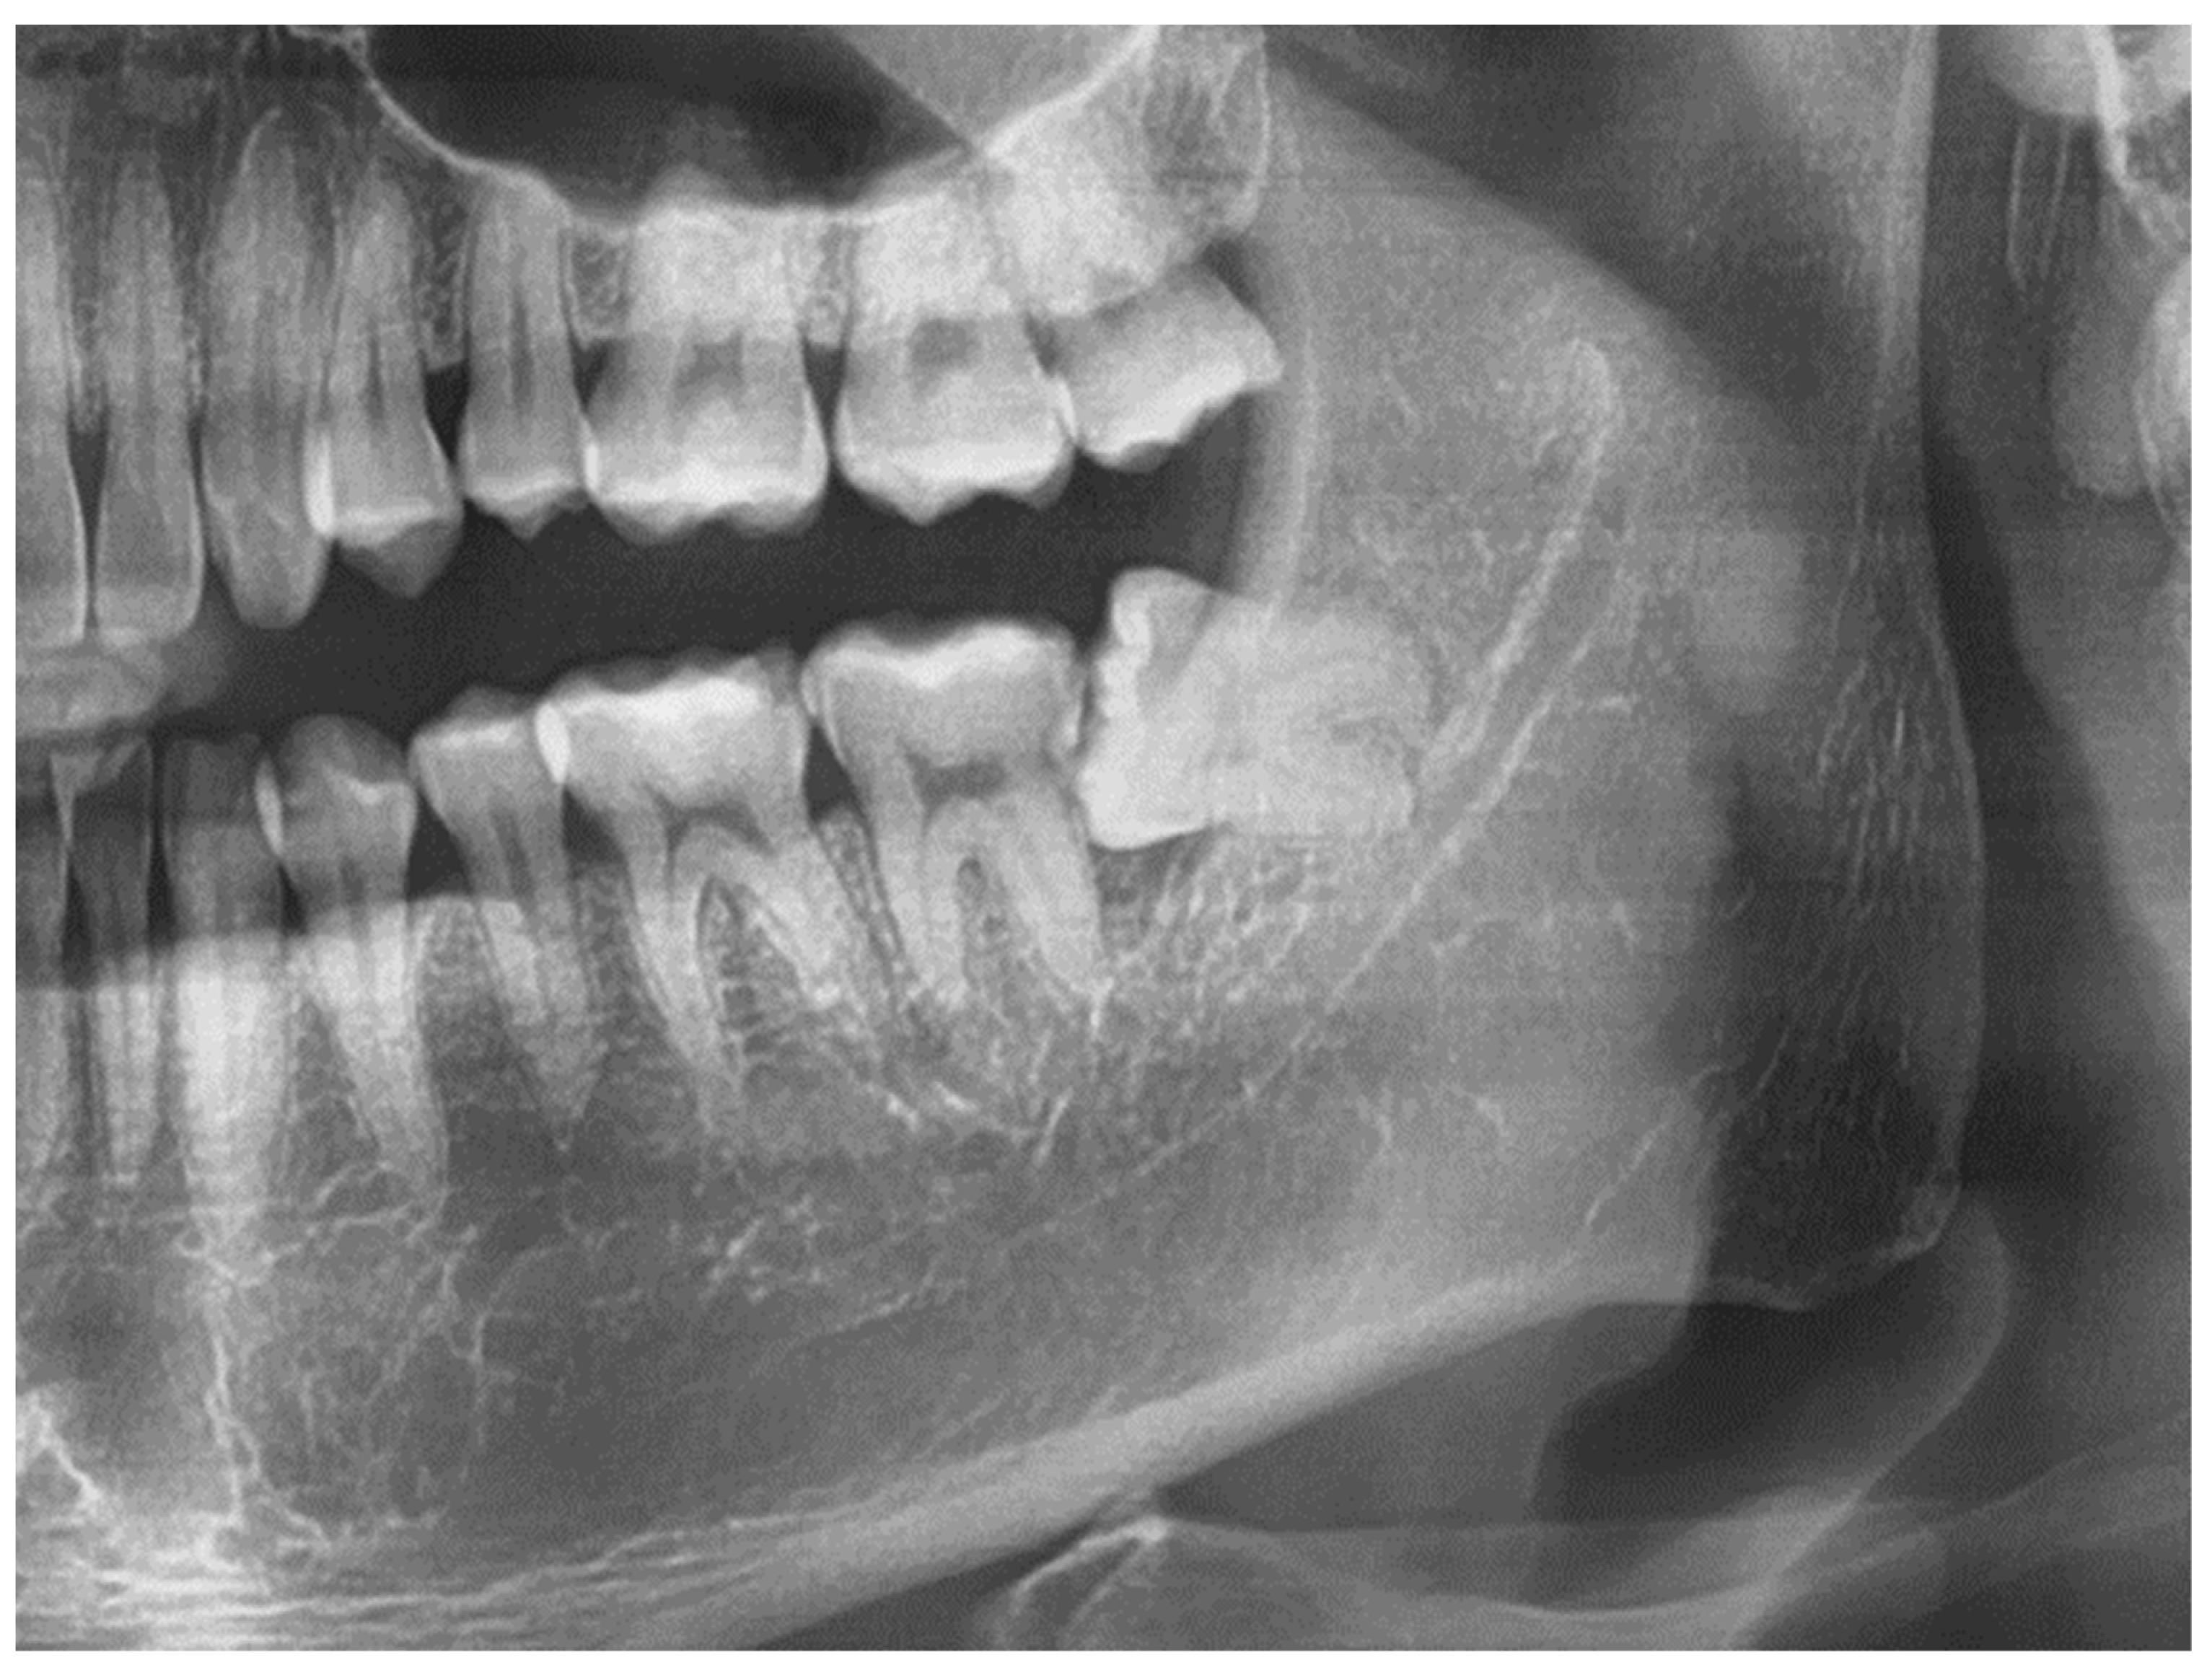

- Dark-group (D-group): The pre-operative OPG of patients who had a dark area at the apical portion of the root/roots of the inferior third molar;

- Control-group (C-group): The pre-operative OPG of patients who did not present a radiolucent area at the apical portion of the root/roots of the inferior third molar.

- True sign (Y-sign): the pre-operative OPG shows a band-like radiolucent sign corresponding to the apical portion of the root of the inferior third molar with no sign of other reason that could explain this. On CBCT image lingual impaction of the root is observed.

- False sign (F-sign): OPG image shows a band-like radiolucent area corresponding to the apical portion of the root of the inferior third molar and determining causes of the radiolucent area visible on OPG and CBCT such as Juxta-Apical Radio-Translucency, peri-apical lesion, immature apex, impaction of the inferior alveolar nerve into the lingual plate, apex impaction into the buccal plate.